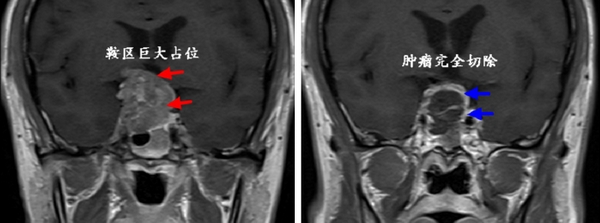

经过充分的术前准备,在麻醉科、手术室的协作下,王刚副主任为其采用神经内镜技术成功切除了肿瘤,术后李先生视力恢复正常,激素项目检查提示垂体功能正常,复查核磁显示肿瘤全部切除。三天后,李先生就痊愈出院,重新开始了他的正常生活工作。